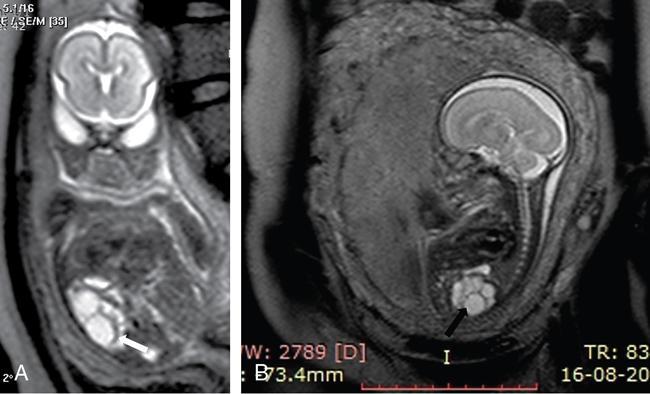

Priscilla Joshi, Vandana Jahanvi Renal anomalies encompass a spectrum which ranges from the lethal renal agenesis to incidentally detected renal anomalies secondary to aberrant embryonic migration. Imaging helps in the early diagnosis, detection of complications, surgical planning and follow-up of these patients. The kidneys develop from the pronephros, mesonephric and metanephros. These succeed each other. The intermediate mesoderm develops into the pronephros at the end of the 3rd week of gestation. This regresses a week later and is replaced by the mesonephros. The kidneys develop during the 4th week of gestation. The ureteric buds fuse with the metanephros. This occurs at the level of the first two sacral segments. In the pelvis, the kidneys are close to each other with the hila directed anteriorly. Over the next 4 weeks, the kidneys ascend into the lumbar region and move away from each other as well as rotate medially so that the hila are medially and anteriorly directed. Congenital urinary tract anomalies range from anomalies in number, anomalies in shape, cystic renal disease, collecting system anomalies and urinary bladder anomalies. These will be discussed one by one in this section. In renal hypoplasia the kidneys are small. They show a normal architecture, but the number of nephrons is reduced. The condition can be unilateral or bilateral. If unilateral the contralateral kidney shows compensatory hypertrophy. Hypoplasia if bilateral is part of genetic syndromes like renal coloboma syndrome and branchio-oto-renal syndrome. It can result in end-stage renal disease because of the reduced number of nephrons. US: A kidney which is smaller by 2 Sd as compared to the mean kidney size expected at that age. Radionuclide scan (DMSA): Rules out scarring. Less than 100 cases of this anomaly have been reported in literature. This is an extremely rare anomaly. The accessory kidneys are usually seen on the left, caudal to the left kidney. Accessory kidneys are usually smaller in size and show suboptimal function. They can be detected on ultrasound and confirmed with cross-sectional modalities like MR urography/CT urography. Function can be evaluated on postcontrast CT/MR urography or with dimercaptosuccinic acid (DMSA) and diethylene triamine penta-acetic acid (DTPA) scans. Associated urogenital or other anomalies maybe be seen. Incomplete fusion of the developing renal lobules causes a lobulated appearance of the kidneys. This has to be differentiated from renal scarring. Persistent foetal lobulations are seen as a smooth indentation of the renal outline. This is seen between the renal pyramids on ultrasound whereas the indentation in scarring overlies the renal pyramids and is not smooth and symmetrical. This can be appreciated on US, CT and MRI. This occurs due to prominent renal cortical tissue between the pyramids extending towards the parenchyma. It can mimic a renal mass on ultrasound. The interpolar region of the left kidney is a common site. It can be differentiated from a mass as it is in continuity with normal renal parenchyma and shows the same appearance as the rest of the renal parenchyma on all imaging modalities. This is a normal variation in the contour of the left kidney. The lower pole of the spleen causes an impression on the superolateral aspect of the kidney, which can mimic a renal mass. It shows the same echogenicity/density and signal intensity as the rest of the kidney. Postcontrast images on CT and MR also show enhancement akin to the rest of the kidney. Also, the calyces extend further laterally into the hump as compared to the other calyces. Infolding of the cortex at the level of the renal sinus can appear as a pseudomass, known as the renal hilar lip. As in the case of the dromedary hump the imaging characteristics of this lesion being akin to the rest of the renal tissue help reaching a diagnosis. This occurs due to embryonic fusion of renunculi. It is a normal variant which is located in the interpolar region. It occurs due to extension of sinus fat into the cortex and is seen as a triangular echogenic area on ultrasound which is in contiguity with the renal sinus fat. Differential diagnosis can include a renal angiolipoma which on ultrasound is well defined, echogenic, round, and is not in contiguity with the renal sinus fat. Simple renal cysts are rarely seen in children. An underlying genetic cystic disease or rarely a malignancy needs exclusion. The diagnosis of a simple cyst should be one of exclusion. At least one follow-up ultrasound should be done to evaluate change in size and imaging appearance as well as to rule out development of additional cysts. Further cross-sectional imaging evaluation with CT and MRI and contrast studies are not required unless atypical findings are seen initially or on follow-up. This is a severe form of renal dysplasia which may be unilateral or bilateral. Renal dysplasia occurs due to abnormal metanephric differentiation. It has an incidence of 0.3 to 1 in 1000 live births. When bilateral it is incompatible with life. The kidney is not reniform and is composed of multiple cysts of varying sizes which are noncommunicating. There is no visible functioning renal parenchyma appreciable. The collecting system and ureter are both not seen/atretic. The condition is now being detected more often on antenatal ultrasound foetal MRI (Fig. 10.7.1). The contralateral kidney, if normal, shows compensatory hypertrophy. Sequelae such as hypertension, proteinuria and renal impairment are uncommon as is contralateral VUR, PUJO. There is no increased incidence of malignancy reported. US: Multiple cysts of varying sizes which are noncommunicating are seen. The kidney may be enlarged and even palpable in neonates. Subsequently, the kidney may involute. The contralateral kidney shows compensatory hypertrophy. CT/MR: It shows similar findings. The kidney is nonfunctioning on postcontrast CT/MR or a DMSA scan. The ureter may be atretic. ARPKD is a paediatric cystic renal disease with an incidence of 1 in 10,000 to 40,000 live births. There is no gender predilection. This condition results from mutations in the PKHD1 gene on chromosome 6p12 that encodes for the protein fibrocystin. The earlier the diagnosis is made the condition will be more severe. This condition manifests itself at the age of 30–40 years. It is one of the most common genetic disorders caused by a single gene mutation with an incidence of 1 in every 1000 individuals The kidneys are enlarged (Fig. 10.7.4) and contain multiple cysts of varying sizes. There is deterioration of renal function leading to renal insufficiency. In the neonate, the cysts may be very small and discrete. In children without a genetic diagnosis or a clear family history where the condition is detected, a follow-up USG should be performed within 12 months of the initial detection.

Multicystic dysplastic kidney

Imaging findings (Fig. 10.7.2)